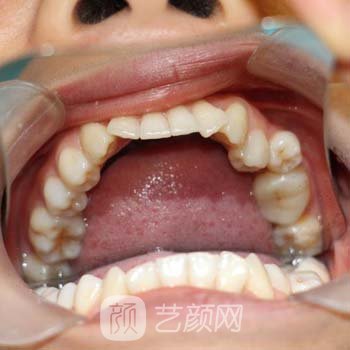

嘴里少了一個(gè)牙齒,和別人說話或者笑的時(shí)候都很不自然。我經(jīng)常捂嘴,尤其是別人看我眼睛的時(shí)候。因?yàn)榕滤闯鑫疑倭艘活w牙,所以自卑。在網(wǎng)上看到很多關(guān)于種植牙的新聞,所以對種植牙有一定的了解。做好準(zhǔn)備后,我決定種植牙齒。

于是我來到了無錫通善口腔醫(yī)院。和醫(yī)生談過之后,我選擇了一個(gè)性價(jià)比高的牙齒。醫(yī)生說,牙齒植入現(xiàn)在較為普遍,技術(shù)也很成熟。如果植入的牙齒恢復(fù)得好,果會和真牙一樣強(qiáng),植入的牙齒的牙齒形狀會像真牙一樣根據(jù)大家的牙齒,來決定,不用太擔(dān)心。聽了醫(yī)生的話,我忐忑的心得到了極大的安慰,我也不再緊張了。

醫(yī)生首先給我的牙齦打了麻藥。麻醉果出來后,醫(yī)生小心翼翼地在我的牙齒,上做了一個(gè)切口,然后慢慢地把人工牙根放進(jìn)去,耐心地為我縫合了整個(gè)過程。醫(yī)生的技術(shù)較為熟練,手術(shù)在一個(gè)多小時(shí)后結(jié)束。我沒覺得疼,只是打麻藥的時(shí)候有點(diǎn)疼,但是都還可以忍受。醫(yī)生說,這只是手術(shù)的第一步,下一步是一個(gè)漫長的等待過程。當(dāng)我的假牙和牙齦牢固地長在一起后,我會安裝人造牙齒。因此,時(shí)間的長短取決于我的個(gè)人體質(zhì)和我的恢復(fù)果。醫(yī)生還告訴我回家時(shí)要吃流質(zhì)食物。不要用牙齒咬硬的食物,吃得清淡。多注意休息。一定要保持嘴巴干凈。漱口時(shí)要小心。接觸后兩天可能會出現(xiàn)腫脹。這些都很正常,不用太擔(dān)心。一周后來醫(yī)院復(fù)查。然后醫(yī)生給了我一些抗生素,我就回家了。

一周后,我回到了無錫通善口腔醫(yī)院。醫(yī)生看了看我的恢復(fù)情況,發(fā)現(xiàn)還不錯(cuò)。讓我繼續(xù)回家,好好保存,不要吃硬的東西,否則牙齒恢復(fù)不好,可能會造成脫臼。我可以適當(dāng)?shù)爻砸恍┸浭???傊@期間一定要保持口腔清潔,不要?jiǎng)×疫\(yùn)動。三個(gè)月后來醫(yī)院復(fù)查。在這段時(shí)間里,我一直在關(guān)注我的牙齒的恢復(fù)情況,我基本上沒有吃過硬的東西,飲食也特別清淡。主要是不想自己的努力白費(fèi),所以飲食上要控制自己。當(dāng)我回到無錫通善口腔醫(yī)院時(shí),醫(yī)生給我拍了一部電影。我的牙根和牙齦完全融合在一起,所以我可以安裝人造牙齒。

當(dāng)我缺失的牙齦里終于有一個(gè)牙齒的時(shí)候,我是多么幸福啊!這幾天一直期待的時(shí)刻終于到了,終于找回了從前的美好。不,我覺得我現(xiàn)在比以前漂亮多了。我就是太開心了!